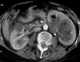

Emphysematous pyelonephritis of left kidney